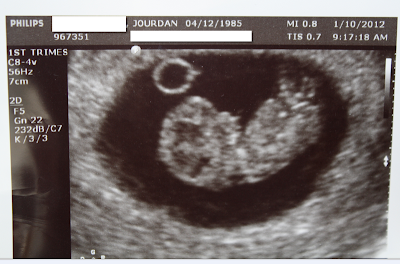

Today is the 10th and we just had our first ultrasound and heard the heartbeat. I'd have to say this was pretty unbelievable. Its still hard to believe this little baby is inside me, even though I totally feel the effects and notice all the changes. As far as my appetite goes lately I've still been craving the same things, citrus and lots of mexican food (but that's typical for me!) And I'm only really grossed out by asian food/flavors right now. Who knows! I swear I can even see a little bump, more like I can't suck it in like I used to! I measured 9 weeks so my due date is august 13th! I'll start doing weekly updates based on Mondays from now on!

At our appointment we had the ultrasound & got to listen to the heartbeat, had an OB educator meeting, and an appointment with my doctor. Here is a picture from our ultrasound...hard to believe this little thing is only the size of a green olive when its actually starting to look like a real baby in this picture! The coolest part of the ultrasound was seeing the actual heart beating. I had no idea that you would be able to see that. Our baby was also moving their little arms around which was really neat! Heartbeat was pretty high at 180 (but in the normal range for this early).